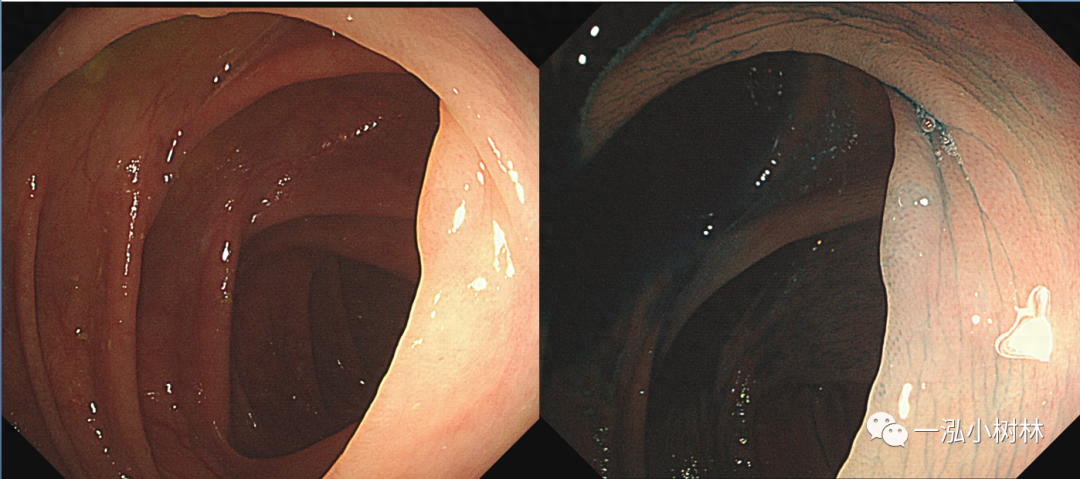

图2 结肠管状腺瘤(Pit Pattern IIIL型)